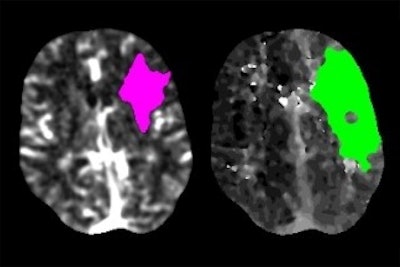

Scans of a stroke patient's brain show the area where tissue has died (magenta) and where tissue is damaged but may still be saved with prompt intervention (green). Image courtesy of Dr. Akash Kansagra.Kansagra and colleagues had access to a data repository of 231,753 patients whose scans were analyzed with the Rapid software, and they calculated the number of scans performed on a daily basis from July 2019 through April 27, 2020. In particular, they compared daily use of Rapid during a 29-day period before the pandemic in February 2020 with a 14-day period from March 26 to April 8.